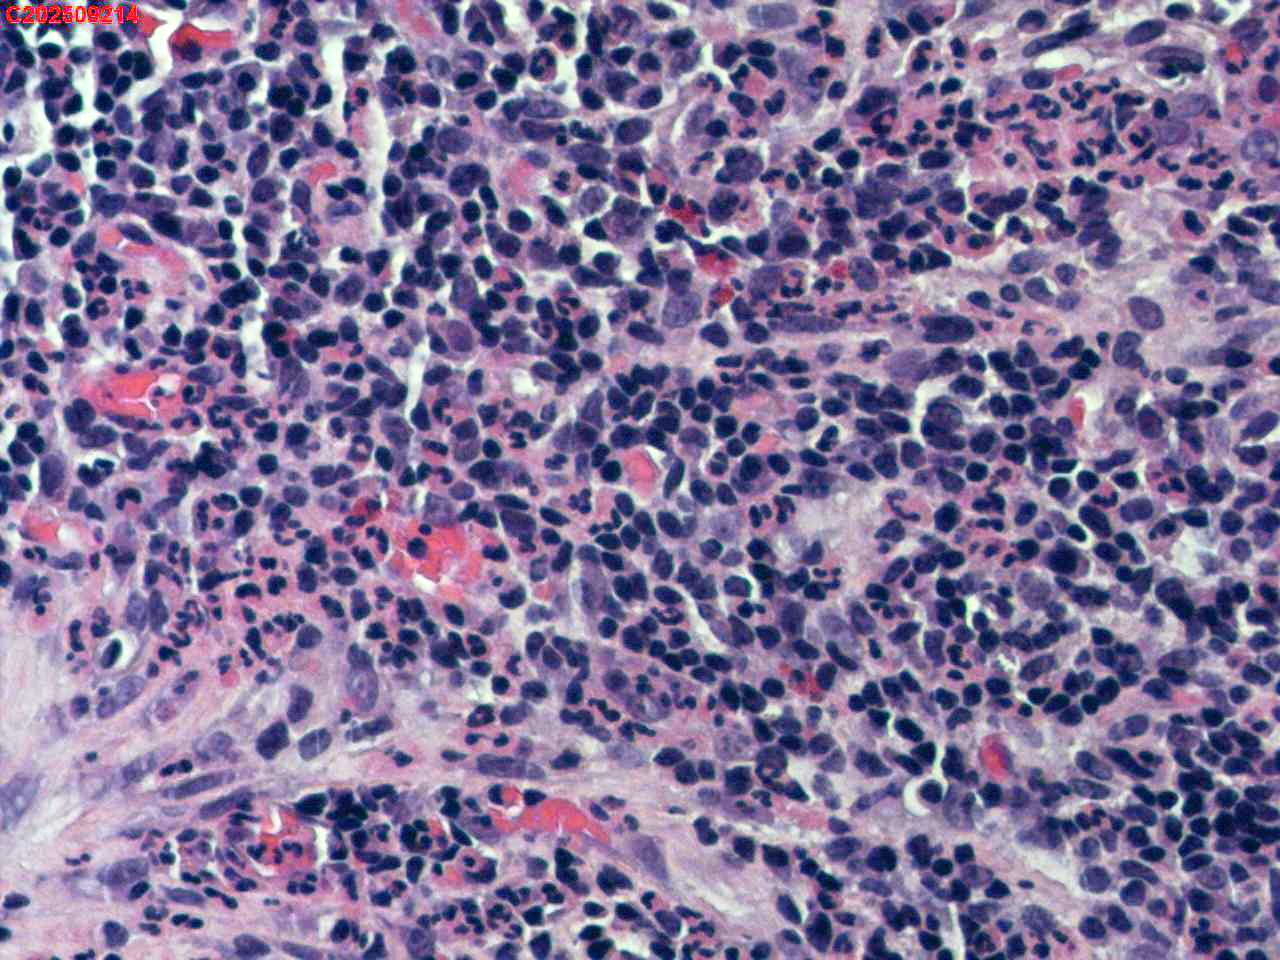

左肺下叶背段咬检组织

性别年龄59岁临床诊断肺结核?肺部感染?

一般病史胸部(平扫):两侧胸廓对称,气管及纵隔居中。双肺纹理增多、紊乱,胸膜下区见多发索条影;双肺见多发大小不等斑片状高密度影,部分呈树芽征样磨玻璃样改变,部分病灶内见支气管含气、少许钙质沉积。气管及大支气管通畅。心脏大小形态可;冠状动脉走行处见多发条形高密度影。双侧胸膜局部肥厚粘连。纵隔内见多发淋巴结影,4L区较大者约10mm* 16mm。

标本名称左肺下叶背段咬检组织

大体所见纤支镜检查:左肺主支气管上叶、下叶及各段级支气管通畅,粘膜无充血,背段外亚段远端可见疑似白色痰栓,灌洗支气管刷检并镜下尝试活检钳清理,发现其质硬考虑为新生物并咬检,该部位深远,且咳嗽及呼吸干扰取材不理想。

毛霉菌病